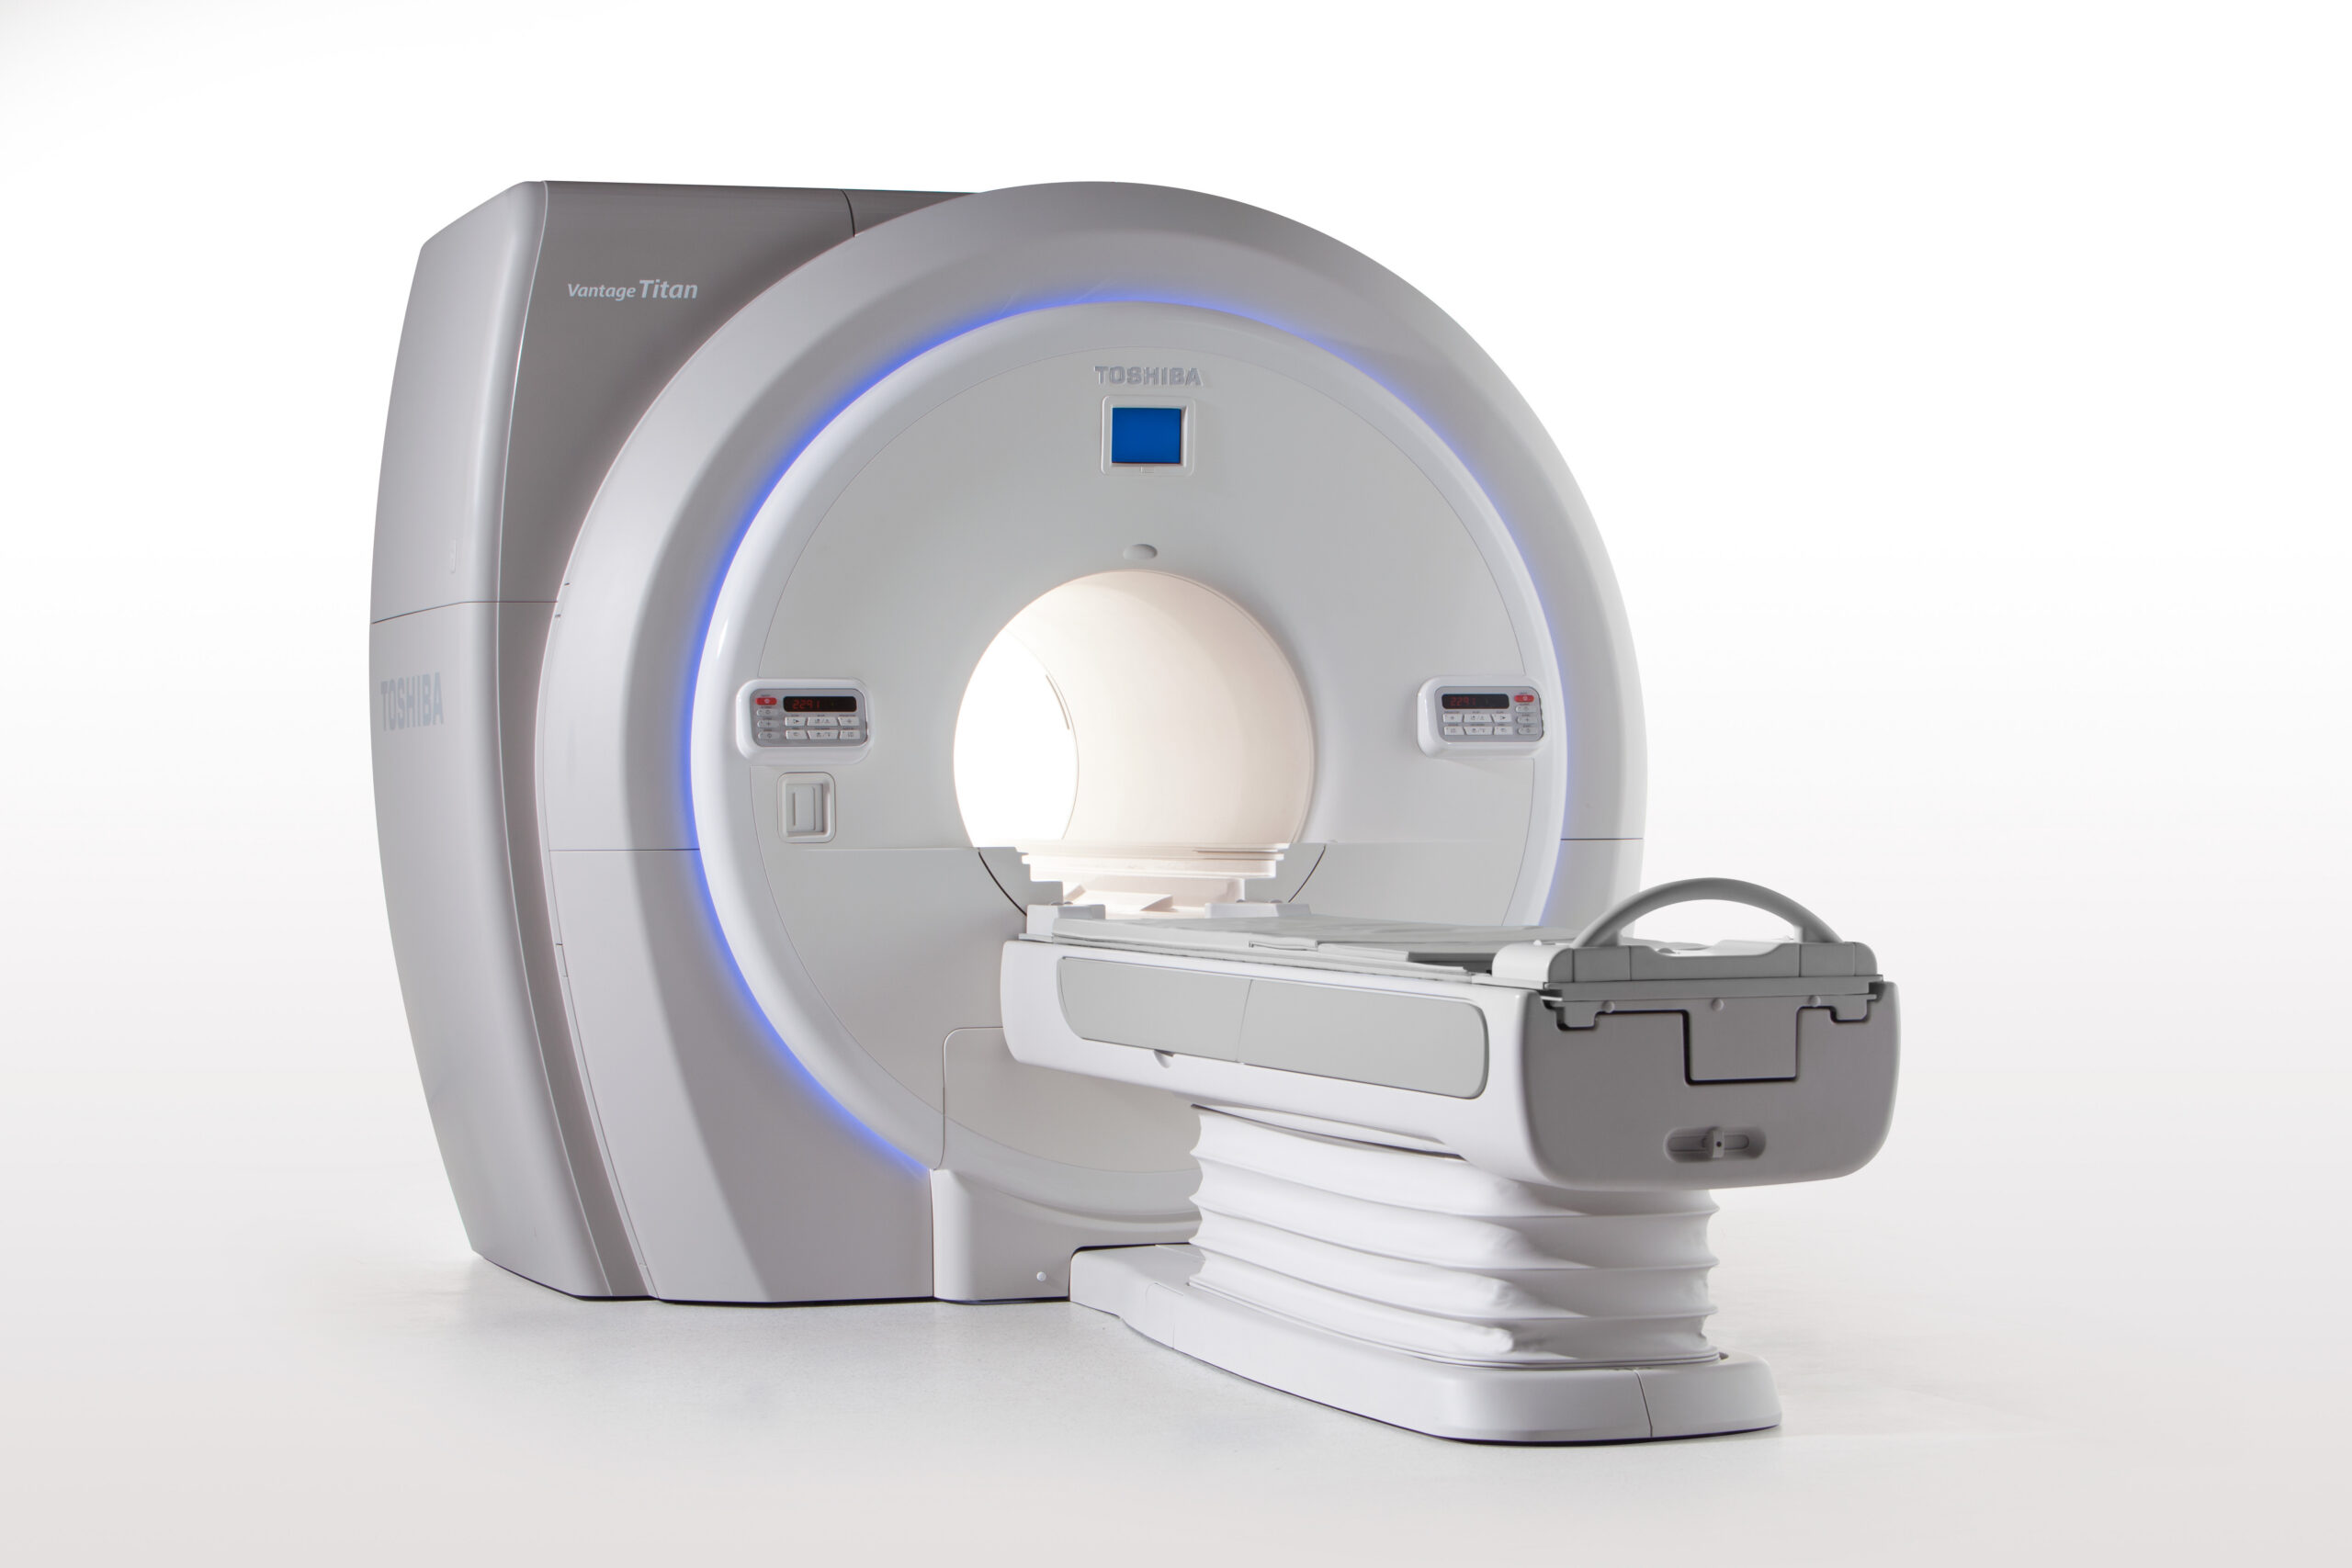

Products

We provide reliable service for our partners all around the globe. Offering well-known brands such as Fujifilm Healthcare, Carestream Health, Konica Minolta Healthcare and many others. Minimum order quantity is 1 pallet.